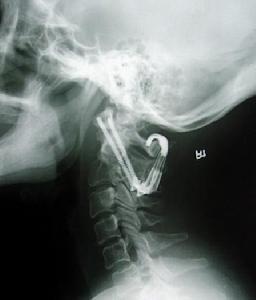

寰樞關節脫位除外上頸椎的其他部位損傷,必須藉助X線攝片X線張口位攝片,主要特徵表現是樞椎齒狀突與寰椎兩枚側塊間距不對稱。但張口拍片時合作不好可使投影位置偏斜,引起兩者間隙異常,或不能滿意顯示該區解剖結構。必要時多拍幾次片,排除因投影位置不當造成誤診,側位X線片能清醒顯示齒狀突和寰樞椎弓之間的距離變化。正常情況下在3mm以內,必要時CT掃描,與寰椎椎弓骨折及上頸椎畸形鑑別。應注意嚴重的陳舊性半脫位,表現為斜頸及運動受限,頸部活動時疼痛。可導致面部發育不對稱斜,頸的出現可引起對側胸鎖乳突肌痙攣。

其次,橫韌帶是軟組織:在普遍X線不能顯影,其損傷情況應以間接影像加以判斷,寰椎前弓結節後緣中點至齒狀突距離(ADI)比較有用。

(1)寰齒間距增大:側位片可見寰椎前弓後緣與齒狀突相對應點的距離,正常成人和兒童分別為3mm和4mm,如成人寰齒距為3mm-5mm之間,常提示有橫韌帶撕裂。如寰齒距為5mm-10mm則提示橫韌帶有斷裂,並部分輔助韌帶撕裂,如10mm-12mm則證明全部韌帶斷裂。

(2)枕頸伸屈功力性側位片:顯示屈位時寰椎前弓和齒狀突呈“V”型間隙,提示橫韌帶下纖維以外的部分撕裂,使寰樞椎藉助未斷纖維束起支點作用,而顯示寰齒間隙上部分分離呈V型。

(3)枕頸伸屈動力性側位片,顯示寰椎前後不穩徵象,確診為韌帶損傷。

1、X線檢查: